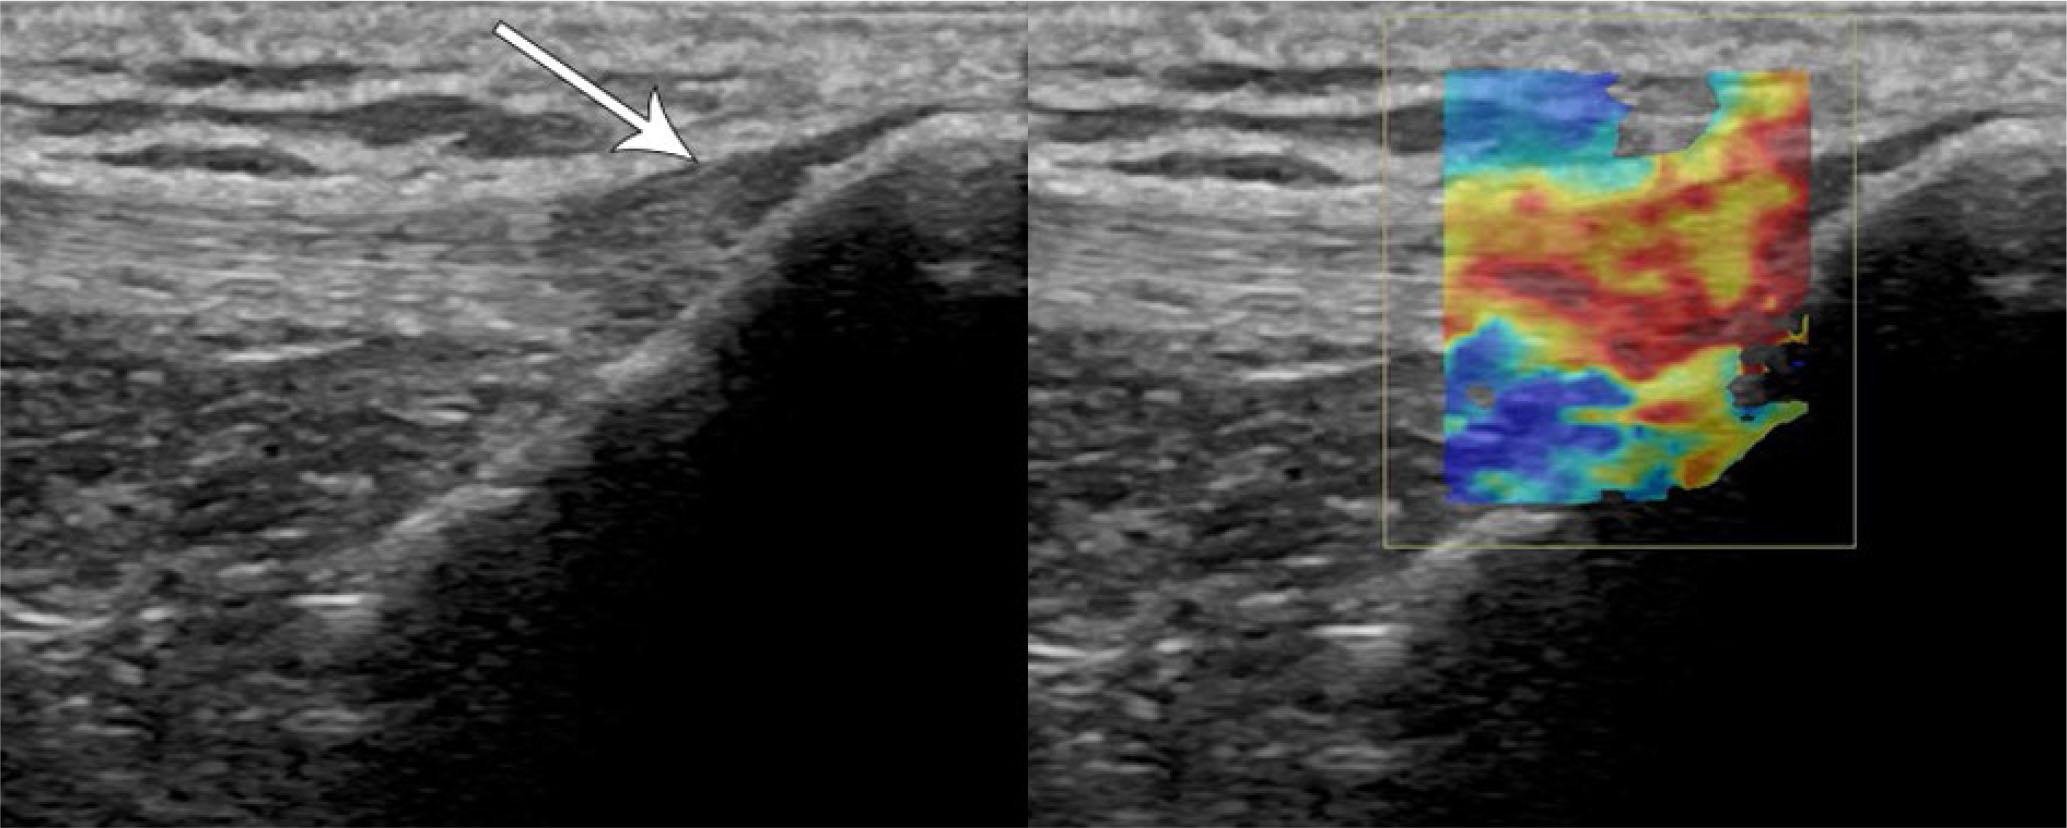

The use of Doppler imaging and elastography increases the sensitivity for the detection of tendinosis with higher tendon stiffness in symptomatic patellar tendinopathy (Fig. 16)(52,53). Studies demonstrating the evolving elastography properties of the patellar tendon following ACL graft harvesting reveal the future promise in assessing tendon healing in the post-operative and post-traumatic settings(54,55). This is particularly helpful, as patients may experience symptomatic and functional improvement in the absence of morphological changes on grayscale US, and measurable improvements in tendon stiffness may help predict outcomes and track recovery(56).

Fig. 16.

65-year-old female with anterior knee pain. Longitudinal grayscale and transient elastography US images of the distal patellar tendon show focal hypoechogenicity and thickening (arrow) with corresponding increased stiffness denoted by overlying color map (increasing stiffness from blue to red), consistent with focal patellar tendinosis